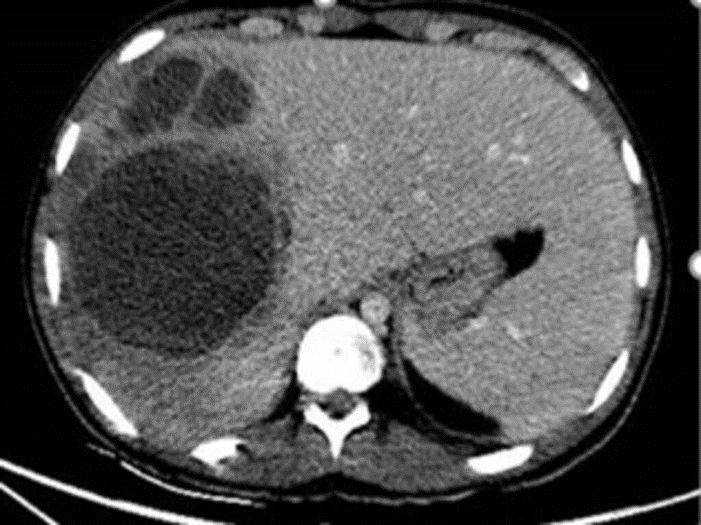

Абсцесс печени кт

Абсцесс печени кт 109 фото